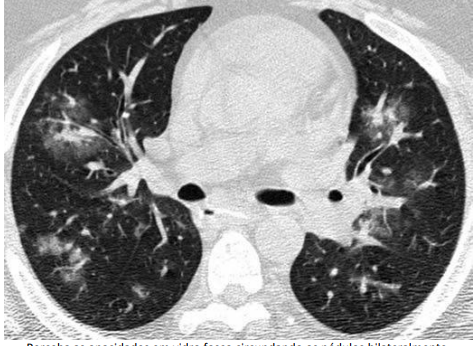

Q

Sinais e padrões torácicos

Qual padrão da imagem?

A

Padrão de árvore em brotamento

* Perceba que poupa as regiões subpleurais